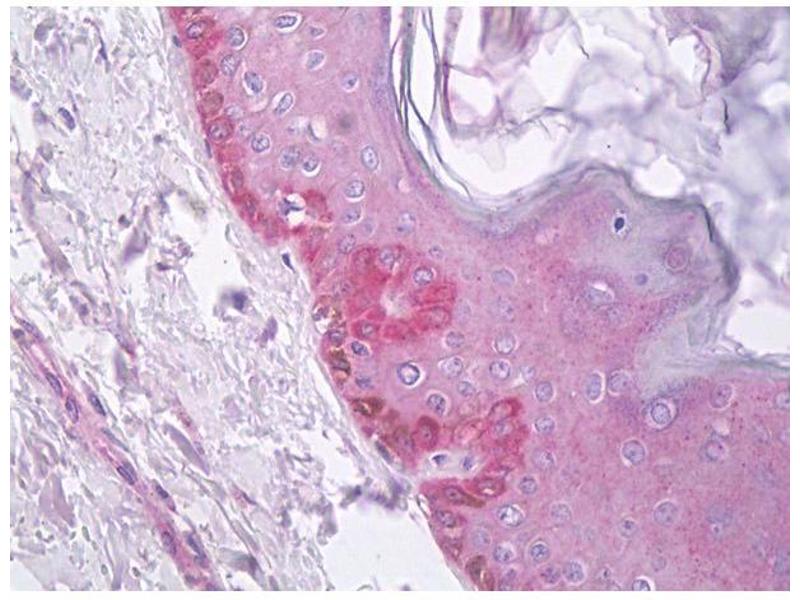

- IHC : 1/50 to 1/500 - WB : 1/200 to 1/2 000 -